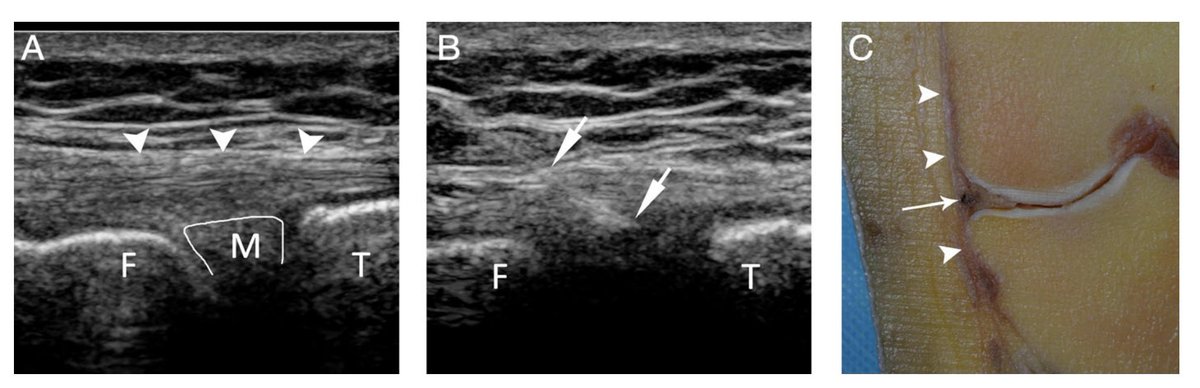

Congrats to @Cronin90Kevin on leading this along with @DrSOF_ and @EamonnDelahunt; we are delighted to present this paper on T-Junction injuries in @BJSM_BMJ #Imagesinsportsmedicine bjsm.bmj.com/content/early/…